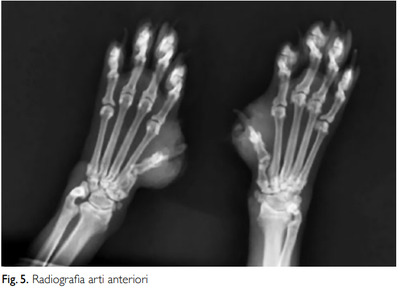

МАТЕРИАЛЫ И МЕТОДЫ КЛИНИЧЕСКОГО СЛУЧАЯ В июле 2017 года на прием была доставлена ОЛЕЗНИ 9-летняя бирманская кошка по кличке Урсула. При осмотре у нее были выявлены множественные очаговые корковые поражения кожи на ушной раковине и переносице, паронихии с отеком третьих фаланг передних и задних конечностей, а также разрозненные пустулы на туловище. ДЕРМАТОЛОГИЧЕСКОЕ ОБСЛЕДОВАНИЕ, проведенное двумя месяцами ранее, 25.05.2017: «Причина обращения: дерматоз. Анамнез: хронический зуд в ушных раковинах и шейно-лицевой области, длящийся более 1 месяца, не поддающийся лечению гипоаллергенной диетой и противопаразитарными препаратами. ЭОП: многоочаговые корковые поражения, расположенные преимущественно на ушных раковинах и переносице. Паронихия с выраженным отеком третьих фаланг кистей и стоп различной локализации. На туловище обнаружено несколько очень маленьких, неповрежденных пустул. Цитологическое исследование: локализация: ногтевое ложе. Внешний вид: казеозный экссудат. Тип образца: соскобы со всех пораженных участков. от паронихии (8 образцов). Описание образца: все исследованные образцы показали отличную клеточность. Были обнаружены многочисленные округлые клетки, иногда с угловатым профилем, центральным ядром и интенсивно базокулярной цитоплазмой, расположенной кластерами или хаотично, наряду с многочисленными недегенеративными нейтрофилы. Цитопатологический диагноз: картина, характерная для листовидного пемфигоида. Ранее назначенное аллопатическое лечение, продолжавшееся на момент обследования (мазь гентамицина сульфата и бетаметазона валерата для местного применения, а также кортизон для приема внутрь), не дало результата, а иногда даже ухудшало состояние. Было решено приостановить текущую терапию и перейти к гомеопатическому обследованию и терапии. Поэтому учитываются не только физические симптомы, но и жизненный контекст животного, предшествующий и семейный анамнез, и, прежде всего, психические и экспрессивные особенности пациента.